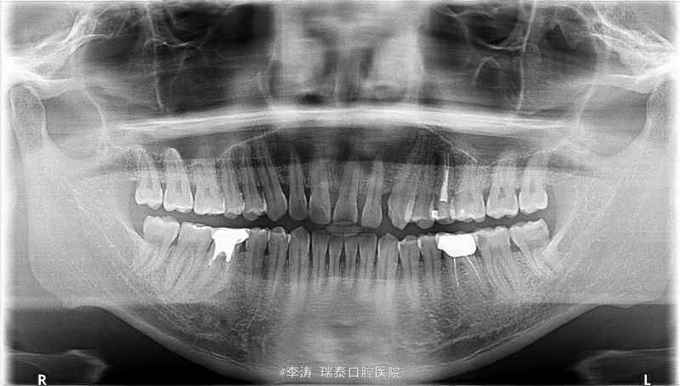

左下后牙龋坏要求补牙

37牙近中深龋,冷-,叩-,x线片近髓